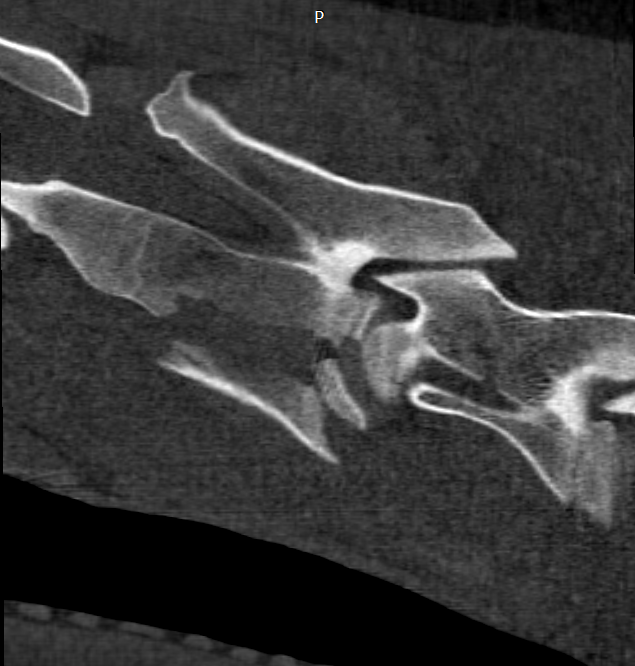

Cervical Fracture - CT and Surgical Repair

Close-up of a fossilized fish in a rock formation.